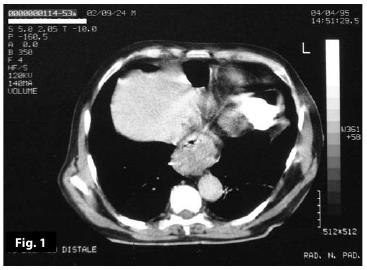

Figure1

Figure1-2